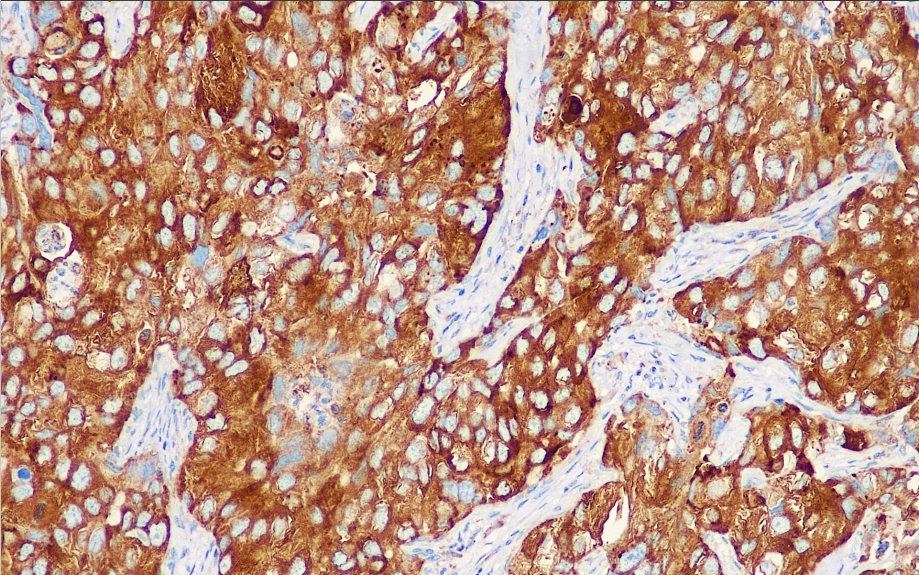

Positive control: Lung adenocarcinoma

The molecular weight of lung cancer drug resistance protein (LRP) is 110kDa. It mainly develops resistance through drug transport disorders between the nucleus and cytoplasm, or by the drug entering the cytoplasmic vesicle to form a locular septum, thereby reducing the effective concentration of the target drug. The expression intensity of LRP in non-small cell lung cancer is significantly higher than that in small cell lung cancer. In non-small cell lung cancer, the expression intensity of lung squamous cell carcinoma and lung adenocarcinoma is higher than that of large cell undifferentiated carcinoma mixed tumors. Studies have shown that LRP is a prognostic reference for testicular germ cell tumors, and its expression indicates a poor prognosis and a short survival period. As a principal protein (MVP) of the fornix, LRP mediates resistance to alkylating agents and platinum that P-glycoprotein and MRP cannot mediate, which is of guiding significance for the selection of chemotherapy drugs.

LRP antibody reagents can specifically bind to LRP antigens. Immunohistochemical kits containing LRP antibody reagents are suitable for the assessment of multidrug resistance (MDR) in tumors such as lung cancer and ovarian cancer.